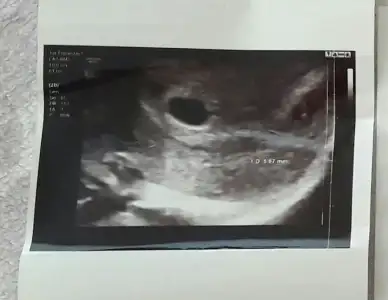

Benimkine de bakar mısınız 6+4

Eklentiler

• AD4A0FA1-C854-4D59-BDBD-415AF455515A.webp

AD4A0FA1-C854-4D59-BDBD-415AF455515A.webp

24,3 KB · Görüntüleme: 107